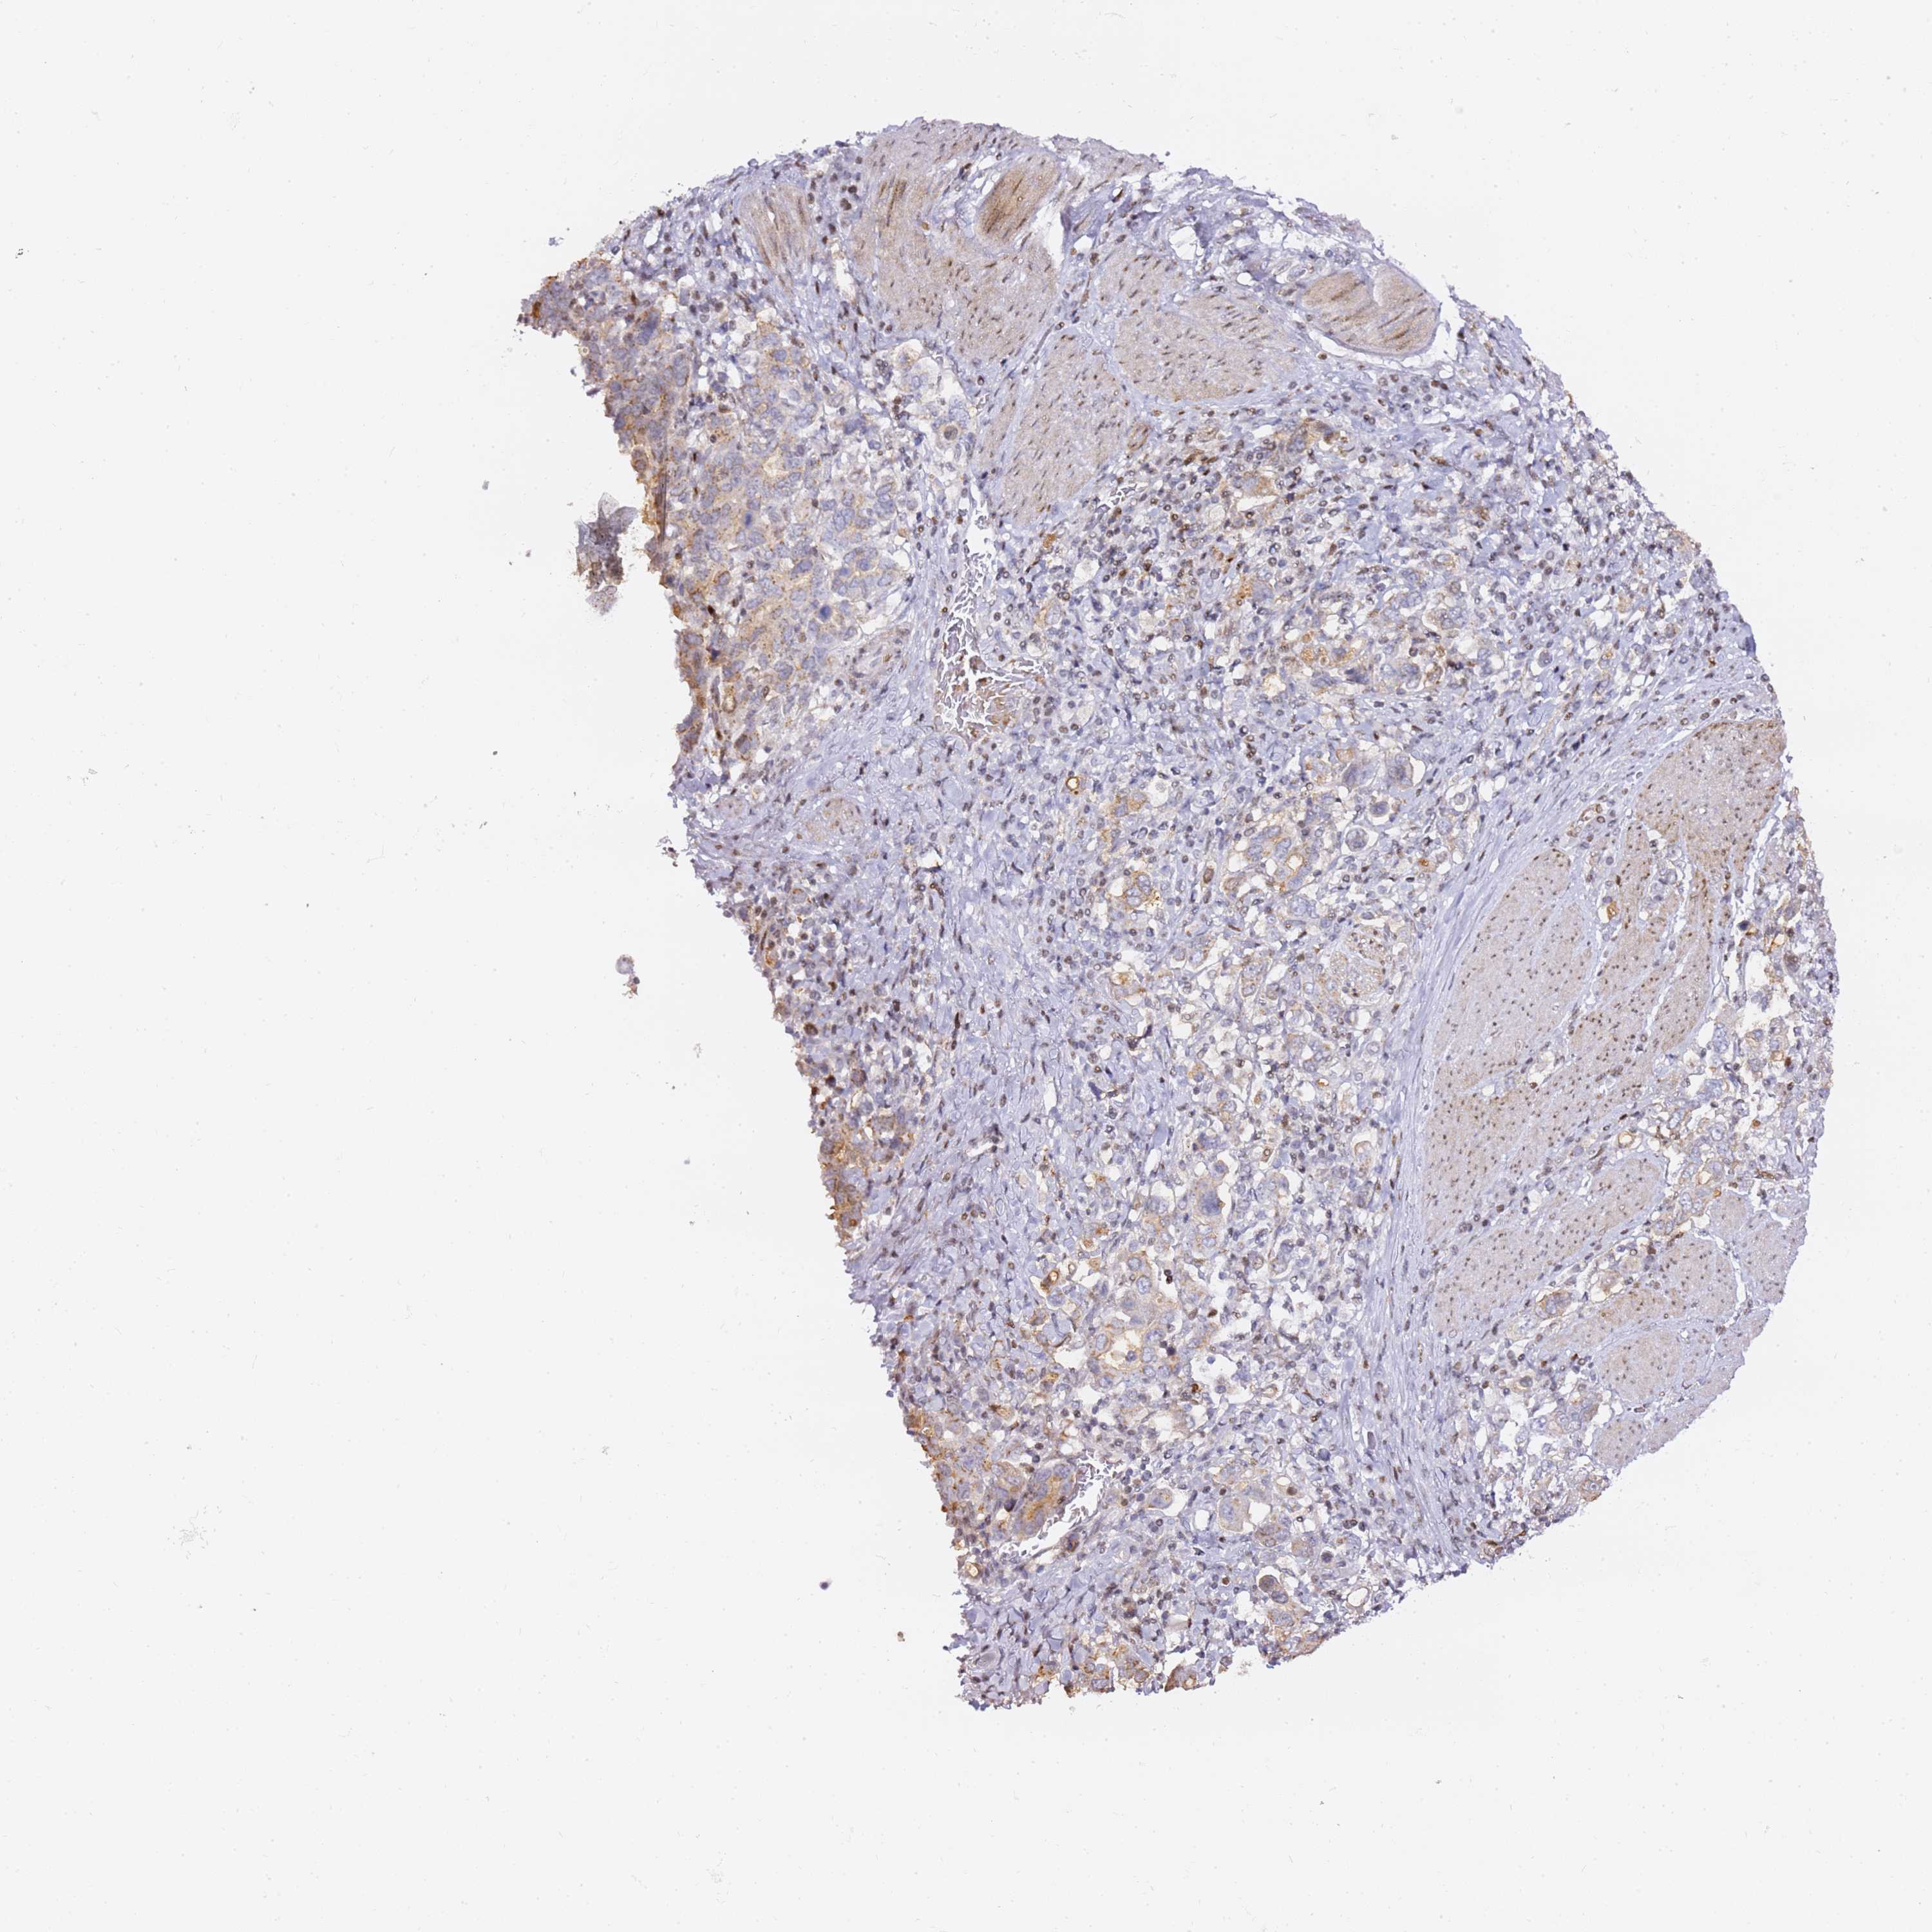

STOMACH CANCER - Protein expressioni

A mouse-over function shows sample information and annotation data. Click on an image to view it in a full screen mode. Samples can be filtered based on level of antibody staining by selecting one or several of the following categories: high, medium, low and not detected. The assay and annotation is described here.

Note that samples used for immunohistochemistry by the Human Protein Atlas do not correspond to samples in the TCGA dataset.

Antibody stainingi

Antibody staining in the annotated cell types in the current human tissue is reported as not detected, low, medium, or high, based on conventional immunohistochemistry profiling in selected tissues. This score is based on the combination of the staining intensity and fraction of stained cells.

Each image is clickable and will lead to virtual microscopy that enables deeper exploration of all samples and also displays staining intensity scores, fraction scores and subcellular localization as well as patient and tissue information for each sample.

Antibody HPA042682

Antibody CAB045975

Staining

High

Medium

Low

Not detected

Intensity

Strong

Moderate

Weak

Negative

Quantity

>75%

75%-25%

<25%

None

Location

Nuclear

Cytoplasmic/membranous

Cytoplasmic/membranous,nuclear

Adenocarcinoma, NOS